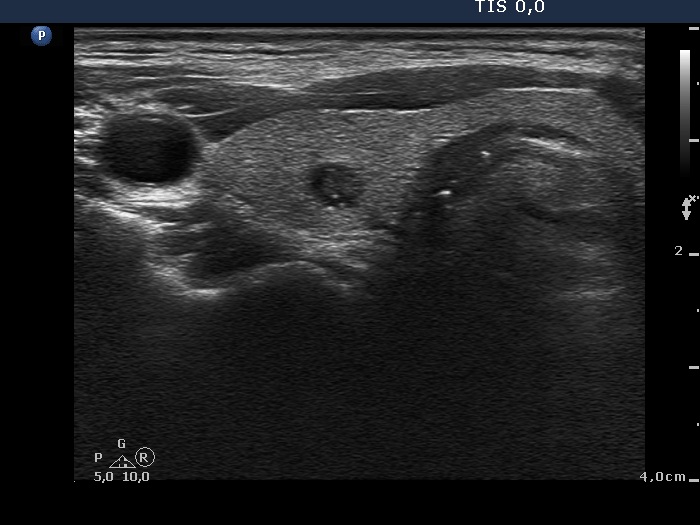

Benign hyperplastic nodules (histological diagnosis) - case 444 |

Papillary carcinoma (histological diagnosis) - case p002 |

Both lesions contain bright granules and lines, i.e. proliferation of connective tissue. The simultaneous presence of punctate echogenic foci (microcalcifications) cannot be excluded in either case. The ultrasound presentation differs in the shape and borders of the nodules. In contrast with the benign lesion, the malignant nodule is lobulated and has blurred borders in its dorsal part.